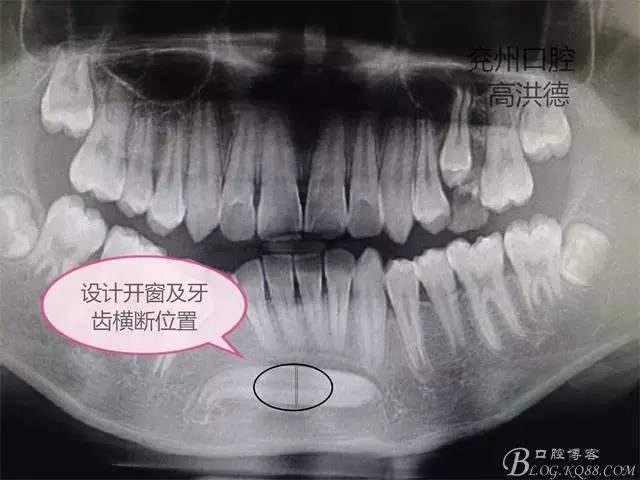

曲面斷層片顯示

手術(shù)設(shè)計(jì);下頜前庭溝做約3CM的切口,分離粘骨膜,高速手機(jī)去骨,暴露牙齒中端,截?cái)嘌例X分別取出,牙冠和牙根。